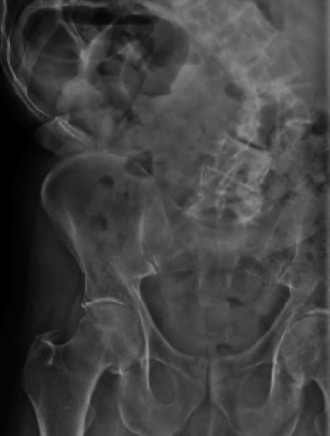

Expected surgical outcomes following revision surgery for recurrent disc herniation? CASE 3 A 27-year-old previously healthy woman is transferred directly to your trauma center with severe low back pain after jumping from an overpass in an apparent suicide attempt. The trauma team completes the primary survey, and the patient is hemodynamically stabilized with fluid resuscitation. On secondary survey she is found to have significant pain with examination/manipulation of her pelvis. Lower extremity examination demonstrates multiple superficial abrasions and grade 4/5 strength with great toe extension and ankle dorsiflexion on the left. Inspection of the perineum shows no blood at the urethral meatus or rectum; however, rectal tone and perianal sensation are decreased. The remainder of the examination is unremarkable. An anteroposterior view of the pelvis demonstrates unilateral superior and inferior rami fractures and a right L5 transverse process fracture.

The correct answer is (C). It is important to recognize that plain radiographs may only detect 30% of sacral injuries. This patient’s plain x-ray findings are highly suggestive of more substantial injuries than isolated rami fractures and transverse process fractures. In fact, the transverse process fracture should be assumed to have occurred by avulsion via the lumbosacral ligaments, which suggests large displacement of the hemipelvis. While plain radiographs may demonstrate sagittal displacement of sacral fractures, they are often of poor quality and do not enable

delineation of the entire fracture pattern. A pelvic computed tomography (CT) scan is indicated to better evaluate the bony injury as well as canal encroachment, particularly in the setting of a neurological deficit. An angiogram might be indicated if the patient was hemodynamically unstable and an intrapelvic bleed was suspected. CT scan images of the above patient are shown inFigures 1–8 and 1–9. Definitive management of this injury should be: 1. 3 months of bed rest followed by progressive mobilization

Figure 1–8 Mid-sagittal image of the pelvis.

Figure 1–9 Axial image of the pelvis.

The correct answer is (D). Critical steps in decision-making include determination of neurologic status, presence of associated pelvic ring injuries, and stability of the lumbopelvic junction. The neurologic examination demonstrates a deficit that is at least in part localized to the sacral nerve roots. In the presence of sacral canal compromise, decompression via laminectomy is indicated. The CT scan demonstrates a U-type injury with a high transverse sacral fracture and bilateral vertical extension through the sacral foramen. In the descriptive classification of sacral fractures in Denis zone 3, H-type and U-type sacral fractures represent spinopelvic dissociation and must be distinguished from fractures localized to the posterior pelvic ring, which are vertically unstable. The spinopelvic junction serves as a critical transitional zone as the axial load of the upper body is distributed from the upper sacrum to the ilium and finally the acetabulum. Surgery is indicated to prevent progressive deformity and chronic pain. Reconstruction should include stabilization from the lumbar spine to the pelvis using a pedicle screw/iliac screw construct. Nonoperative treatment with progressive mobilization is not appropriate for this type of fracture. Plating of the sacrum is not sufficient to restore stability of this injury; nor are sacroiliac screws.